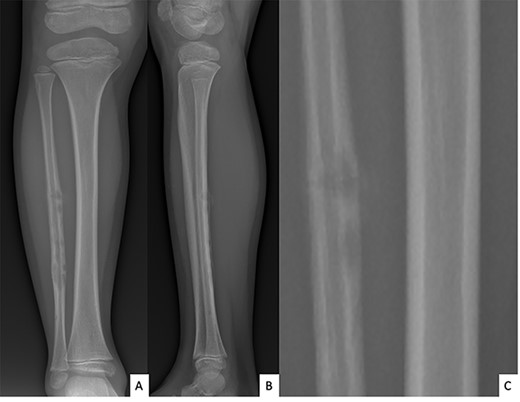

Ultrasound showed a diaphyseal subperiosteal hematoma of the fibula with cortical irregularities. The radiograph showed a pathological fracture, at the upper end of a cortical bone lesion of mixed osteolytic and osteoformative character with bone callus (Fig. 1). MRI showed a multifocal osteolytic cortical process extending along the fibular shaft, without tumor mass in the soft tissues with respect for the signal of the medullary cavity. The perilesional soft tissues were respected, but they appeared in strong hypersignal T2 and enhanced after injection of gadolinium (local inflammatory reaction or post-traumatic changes; Fig. 2).

Anteroposterior (A) and lateral (B) radiographs of right fibula showing pathological fracture on a cortical bone lesion of mixed osteolytic and osteoformative character with bone callus.